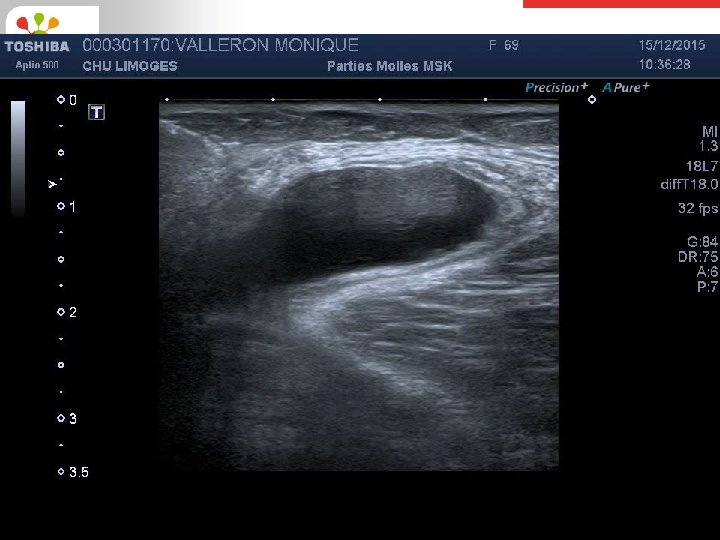

Cas clinique 3 (suite) Masse anéchogène multicloisonnée au niveau de la fosse poplité KYSTE POPLITE SUR GONARTHROSE

Cas clinique 3 (suite) • Volumineux kyste poplité douloureux • Décision d’une ponction-infiltration de corticoïdes (diprostène) sous guidage échographique • Dans un deuxième temps: - Visco-supplémentation